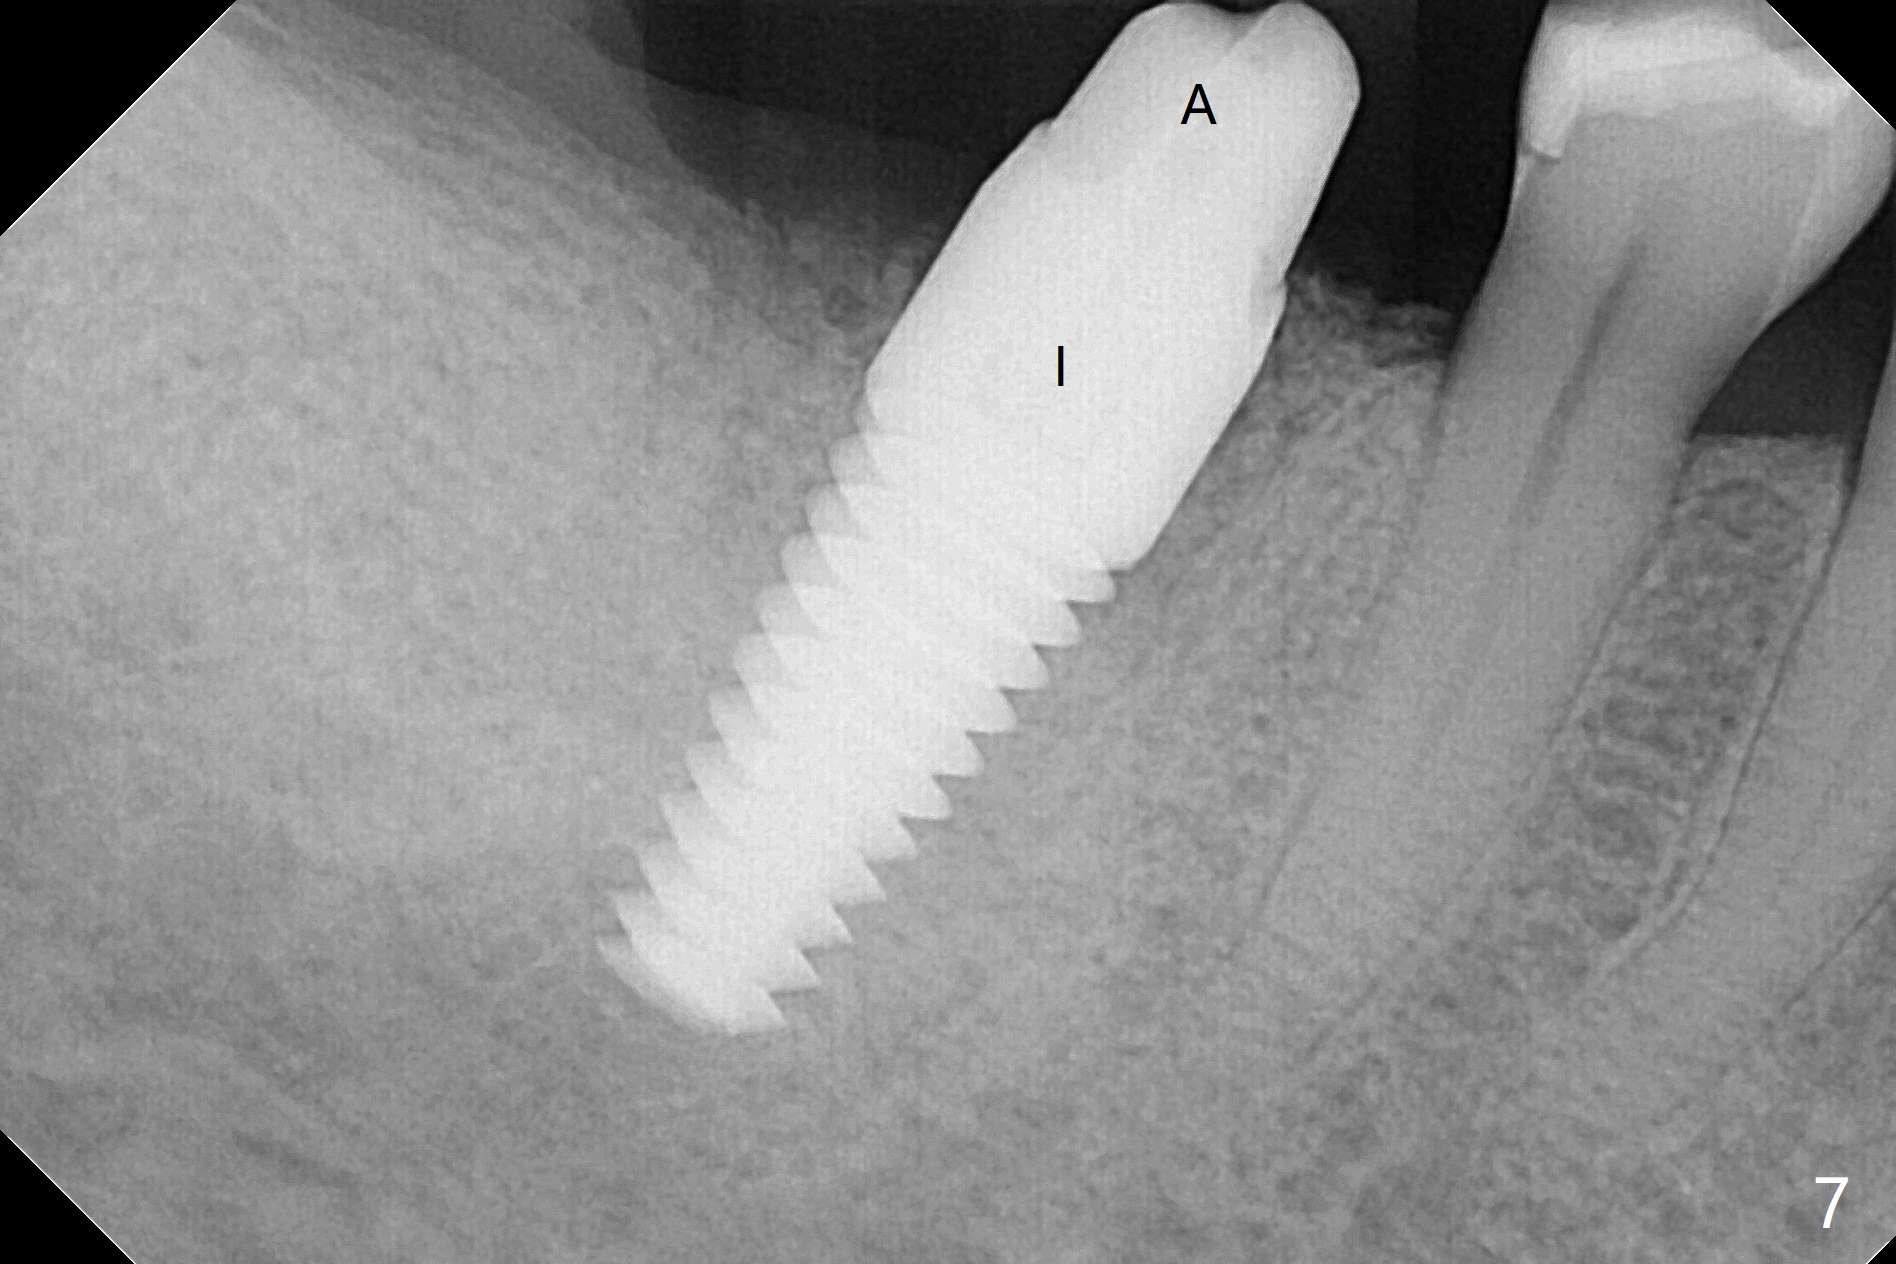

There are signs of periimplantitis at #30 eleven months postop (Fig.1 (* bone loss)). The bony defect (Fig.2) will be filled with allograft mixed PRF liquid to form sticky bone (Fig.3,4), followed by PRF membrane (not shown) and a piece of 6-month membrane (Fig.5). A hole is cut so that the 6-month membrane can slide down the abutment (Fig.2,5 A) to cover the bone graft around the implant (Fig.2,7 I). Setting acrylic is applied around the abutment and neighboring teeth for further protection and holding (Fig.8). The periimplantitis does not resolve nearly 7 months post graft. The implant will be removed. Prepare UF extra wide kit and try to insert 6.5 or 7.0 mm tap. Also prepare sticky bone and Cytoplast for wound closure. Implant removal involves surgical handpiece, 6.2/7 mm trephine bur, elevators, and implant driver. The defect is large (Fig.9) with the low buccal crest (Fig.10) and bone graft with PRF ("sticky bone") is placed, covered by PRF and 6-months membrane (Fig.11). The next implant will be placed with guide. If oral hygiene is not ideal, choose a bone level implant. The middle of the wound dehiscences slightly 8 days postop (Fig.12), accounting for mild loss of bone graft 1 year postop (Fig.14). The keratinized gingiva is apparently wide 1 year postop (Fig.13). There is mild loss of bone graft in the middle of the superficial area (Fig.14). The buccal plate seems to regenerate 1 year postop (pandemic delay, Fig.15).